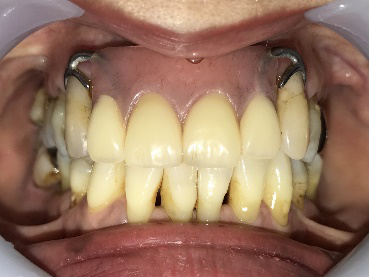

男性Kさん 50代(インプラント)

歯がグラグラするところ、むし歯のところ、しみるところ、被せ物がとれたところ、歯茎が腫れて血が出るところ、歯が抜けているところがある。すべて治したい。

治療内容

残っている歯を抜歯し、上下インプラント治療をしました。

所感

歯周病が進行している歯、むし歯が進行している歯がほとんどで、レントゲンを撮り、詳しく診てみると、ほとんどの歯を保存することができないことがわかりました。抜歯後は、入れ歯かインプラントの方法があります。治療開始前に患者さんに詳しく現状を説明し、治療法についてじっくり相談しました。自分の歯と同じような感覚で食事できるインプラント治療を選択されました。治療後、表情がとても明るくなり、口元がとても自然で10歳以上若返ったように感じました。「時間はかかりましたが、インプラントにして本当に良かったです!」と素晴らしい笑顔でお話ししてくださいました。

上顎:¥3,280,000(税込)

下顎:¥3,280,000(税込)